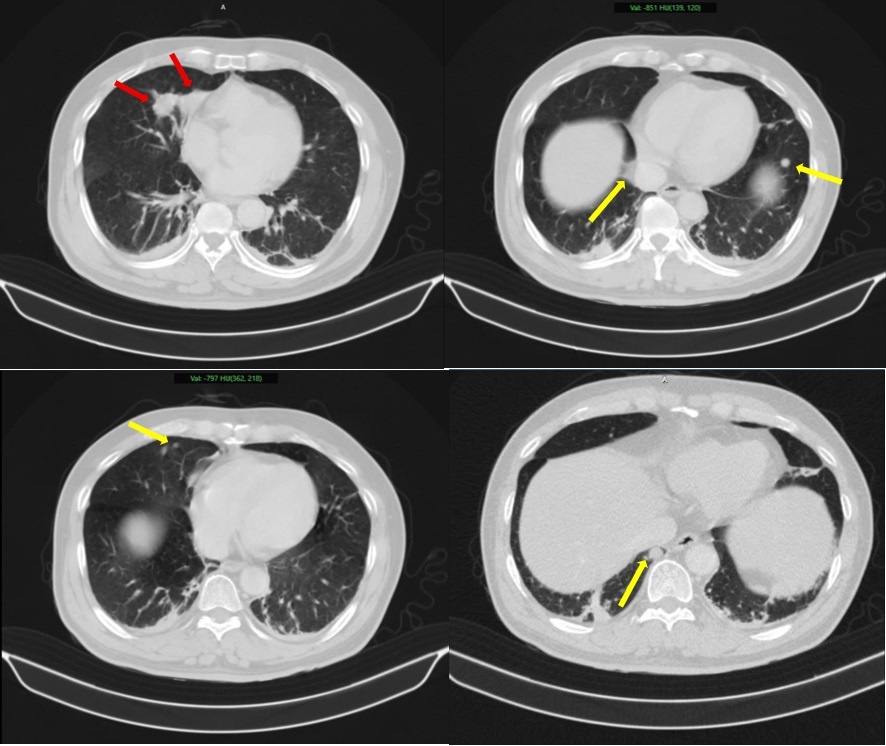

Hình ảnh 2 khối u bờ đa cung ở nhu mô thùy giữa phổi phải, dính vào màng phổi trung thất (mũi tên đỏ) kèm nhiều nốt đặc nhỏ rải rác nhu mô phổi hai bên (mũi tên vàng) gợi ý tổn thương thứ phát. Ảnh: BVCC.

Người đàn ông 63 tuổi đến khám tại Trung tâm Y học hạt nhân và Ung bướu, Bệnh viện Bạch Mai, vì tiểu khó kéo dài. Sau đó, bệnh nhân được chỉ định thực hiện nhiều kỹ thuật cận lâm sàng như chụp cắt lớp vi tính (CT), cộng hưởng từ (MRI), xạ hình xương và đặc biệt là PET/CT. Kết quả cho thấy tổn thương tại tuyến tiền liệt, đồng thời xuất hiện nhiều khối u ở phổi, tuyến thượng thận và xương.

Sau khi tiến hành sinh thiết, phân tích mô bệnh học kết hợp hóa mô miễn dịch, các bác sĩ xác định khối u tại phổi là ung thư biểu mô tuyến của phổi, trong khi khối u tuyến tiền liệt là ung thư biểu mô tuyến với điểm Gleason 9 - thuộc nhóm nguy cơ cao. Hai khối u có nguồn gốc hoàn toàn khác nhau, không phải di căn chéo.